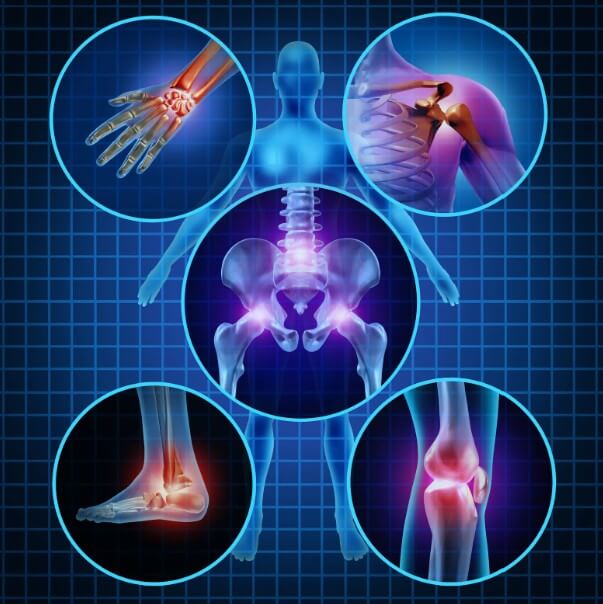

2-3. 무릎·손가락·척추 관절별 증상

| 관절 부위 | 주요 증상 | 특징 |

|---|---|---|

| 무릎 | 걷기 시 통증, 계단 이용 불편 | 관절 모양 변형, 보행 장애 |

| 손가락 | 손가락 통증, 부기, 변형 | 물건 잡기 힘듦, 일상생활 제한 |

| 척추 | 허리 통증, 경직, 방사통 | 신경 압박으로 다리 통증 유발 |

부위별 증상을 파악하면 자신에게 해당되는 증상을 쉽게 인지할 수 있습니다. 증상이 의심된다면 전문의 상담을 권장합니다. 관련 진단법과 관리법을 더 알아보세요.